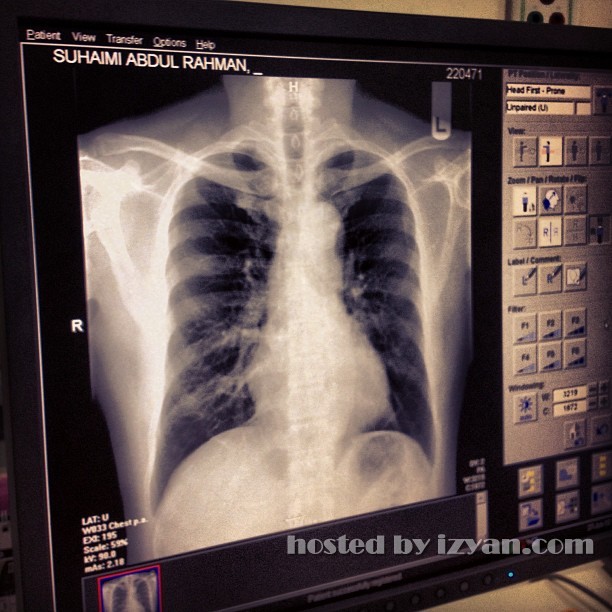

Dikhabarkan raja Rock Negara, Amy Search dimasukkan ke Institut Jantung Negara (IJN) baru-baru ini. Menurut sumber Amy Search ke sana bukan kerana dia menghidap penyakit sakit jantung, tapi hanyalah untuk membuat pemeriksaan jantungnya. Tambahan lagi setelah di periksa oleh doktor dan para pembantunya, Amy disahkan bebas dari penyakit jantung. Syukurlah kalau macam itu. -gambar Instagram Amy Search![]() ![]() ![]() ![]()